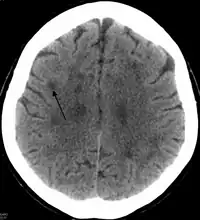

In HDLS, there is enlargement of the lateral ventricles and marked thinning or weakening of cerebral white matter.[6] The loss of white matter is caused by myelin loss. These changes are associated with diffuse gliosis, moderate loss of axons and many axonal spheroids.[1]

Neuroimaging

Standard MRI scans have been performed on 1.5 Tesla scanners with 5 mm thickness and 5 mm spacing to screen for white matter lesions in identified families. If signal intensities of the MRI scans are higher in white matter regions than in grey matter regions, the patient is considered to be at risk for HDLS, although a number of other disorders can also produce white matter changes and the findings are not diagnostic without genetic testing or pathologic confirmation.[2]

Tissue sections from brain biopsies or autopsy brains are commonly embedded in paraffin from which sections are cut and mounted on glass slides for histologic studies. Special stains for myelin and axonal pathology show the abnormal changes that are characteristic of HDLS are identified in white matter of the neocortex, basal ganglia, thalamus, midbrain, pons and spinal cord.[2][10] In addition to routine histologic methods (H&E staining), samples are evaluated with immunohistochemistry for ubiquitin, amyloid precursor protein, and neurofilament to characterize axonal changes and myelin basic protein for myelin pathology. Immunohistochemical stains for microglia (CD68 or HLA-DR) and astrocytes (GFAP) are also helpful techniques to characterize white matter pathology.[6] With a similar pathology to POLD, HDLS is commonly grouped as adult-onset leukoencephalopathy with axonal spheroids and pigmented glia (ALSP) so as to give these individually under-recognized conditions heightened attention.[3]